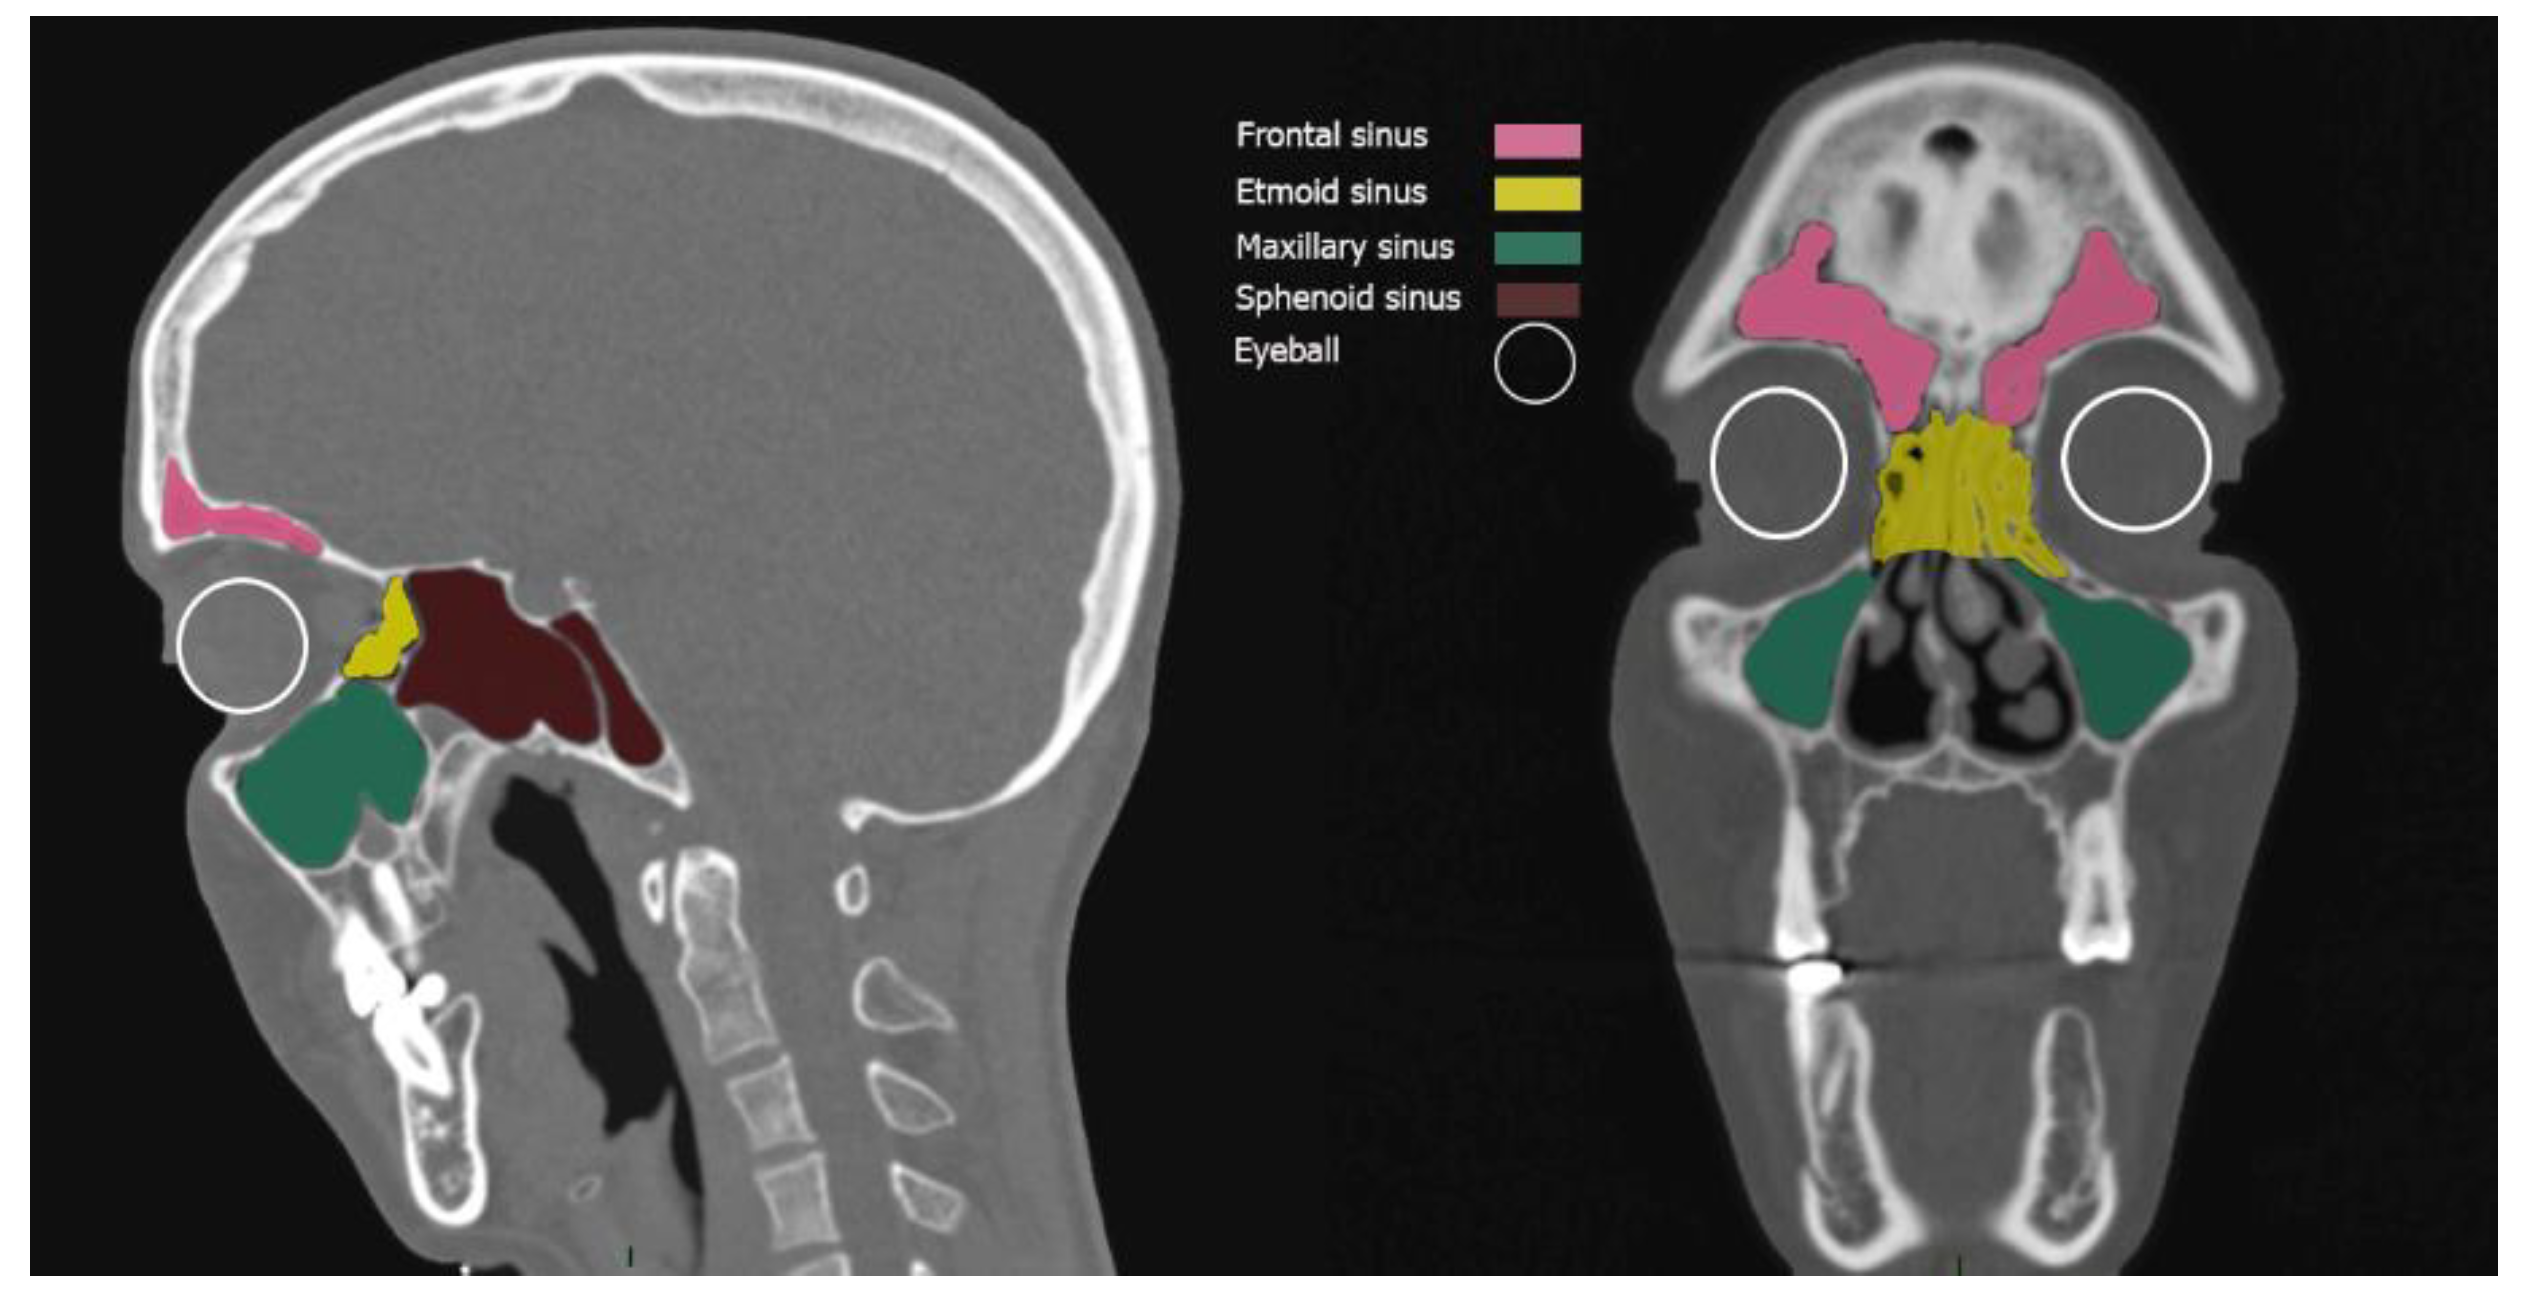

Paranasal Sinuses: The Periorbital Thermal Envelope

Mastoid Air Cells: The Labyrinthine Thermal Shield

Target Structures: Vitreous and Endolymph